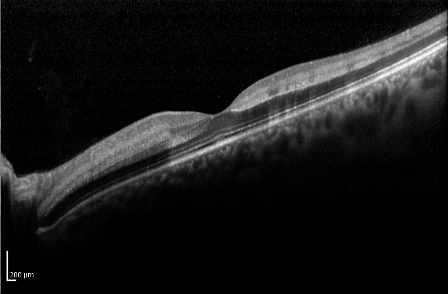

Optical Coherence Tomography

Optical coherence tomography (OCT) is useful in the assessment of macular edema, and particularly in monitoring its course, especially with treatment of the edema.

Typically, the OCT shows cystoid macular edema with or without subfoveal fluid. Epiretinal membrane or vitreomacular traction may also be evident.

In patients with recent-onset CRVO, OCT can detect areas of presumed ischemic edema in the plexiform layer due to ischemia of intermediary neurons within the inner nuclear and inner plexiform layers[10].